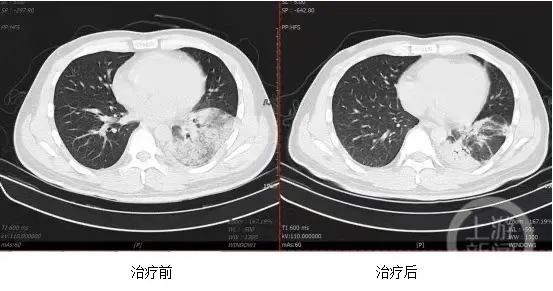

确诊后,在科学的治疗下,该患者的体温很快降至正常,复查胸部CT肺部炎症吸收,病情明显好转,已于近日出院。